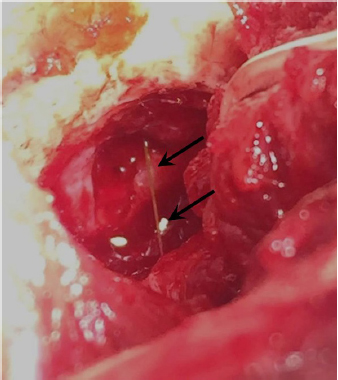

A 3-year-old female Great Dane was referred for acute onset behavioral changes (aggression and disorientation) of 2 weeks duration, and seizures from 24 hours prior to presentation. Physical examination revealed no abnormalities in body temperature, body condition score, heart rate, pulse quality, or cardiopulmonary auscultation. All lymph nodes were considered of normal size and no pain was elicited upon manipulation of the orbital, aural, or cranial musculature. Neither was there any history of dermatological or traumatic lesions in the eye, ear, or mouth. The neurological examination revealed the patient to be obtunded with decreased postural reactions and menace response worse in the left side. Neuroanatomic lesion localization was considered focal in the right prosencephalon with a possible increase in intracranial pressure. Hematological and serum biochemical analysis showed no abnormalities. Magnetic resonance imaging was performed using a low-field magnet (Airis Mate; Hitachi, Tokio, Japan). The study revealed a left-sided single frontal intra-axial lesion affecting gray and white matter adjacent to the internal capsule at the level of the optic canal (Fig. 1). The lesion presented signal homogeneity characterized by hyperintensity on T2W and FLAIR sequences and hypointensity in T1W sequences with peripheral enhancement after intravenous contrast administration (Fig. 1A and 1B). The lesion had a round shape with the greatest diameter of 2.84 cm. This enhancement was also recognized in the surrounding meninges following the brain surface following sulci. A small linear tract observed was directed dorsally from the lesion through the corona radiata (Fig. 1B). The lesion was associated with extensive perilesional vasogenic edema that worsened the mass effect characterized by a midline shift. The orbital and medial pterygoid muscles also showed an intense enhancement (Fig. 2). The wing of the presphenoid bone was thinner than the contralateral bone (Fig. 1B). A CT scan (Astelion 16, Toshiba, Tokio, Japan) was performed after MRI that allowed the identification of osteolysis in the presphenoid bone immediately dorsal to the orbital fissure (Fig. 1C). CT scan also revealed a hypoattenuating intra-axial lesion located in the left frontoparietal lobe together with diffuse hypoattenuation of tissues adjacent to the left optic nerve and the left pterygoid muscle. Finally, CSF analysis showed no abnormalities. On the basis of advanced radiological findings, the main differential diagnosis was an intracranial abscess due to the extension of the extracranial septic process through presphenoid bone. Because of rapid neurologic deterioration and suspected increased intracranial pressure, surgical excision was planned. A modified left rostrotentorial craniectomy was performed. Temporalis muscle and fascia were retracted, extending the incision cranially through the temporal line. Once the frontal and presphenoid bones were exposed an area of osteolysis was observed in the wing of the presphenoid bone immediately dorsal to the orbital fissure. The craniectomy (approximately 3 cm diameter) was centered on the osseous defect. A mucopurulent discharge presented immediately after the incision of the dura mater. A sample was collected for its microbiological study. The surgical site was flushed with sterile saline revealing the tip of a grass awn which was extracted from the brain parenchyma together with a small amount of purulent fluid (Fig. 3). After extensive flushing, the meninges were left open to allow drainage and the incision was closed as per routinely. Postoperative CT showed the correct location of the craniectomy and resolution of the abscess which was substituted by gaseous content but remained inside and on the dorsal surface of the frontal lobe (Fig. 4). Immediate postoperative therapy consisted of amoxicillin + clavulanic acid (Synulox 500, Zoetis Spain SL) 22 mg/kg PO, q8h; marbofloxacin (Marbocyl P80, Vetoquinol SA) 5 mg/kg PO, q24h; metronidazole (Flagyl 250, Sanofi-aventis SA) 15 mg/kg PO, q12h; prednisone (Prednisona Kern Pharma 30mg, Kern Pharma) 0.5 mg/kg PO, q12h; tramadol (Tramadol retard Combix 100 mg, Laboratorios Combix S.L.U) 2 mg/kg PO, q8h; famotidine (Famotidina Normon 40 mg; Laboratorios Normon SA) 0.7 mg/kg PO, q24h; and phenobarbital (Phenoleptil 100 mg, Le Vet BV) 2.5 mg/kg PO, q12h. Cultured samples were positive for Pseudomonas aeruginosa sensitive to ciprofloxacin, imipenem, and amikacin among other antibiotics. Based on these results, antibiotic therapy was changed to ciprofloxacin (Ciprofloxacino 500, Laboratorios Normon SA) 10 mg/kg PO, q12h and metronidazole 15 mg/kg PO, q12h for 2 months. Prednisone, tramadol, and famotidine were withdrawn and phenobarbital was maintained at 2.5 mg/kg q12h. Six-month post-operative revision magnetic resonance revealed no signs suggesting the existence of an inflammatory process (Fig. 5). In the area where the abscess had been located, a fluid-filled cavity suggesting being CSF was observed. One year follow-up revealed the patient had seizures every 3 months with neurological examination remaining normal. The patient died 2 years later of unrelated causes.

Fig. 3. Intraoperative view after left rostrotentorial craniectomy and durotomy above the orbital fissure. Note durectomy and the presence of a grass awn (arrows) overlying brain parenchyma once extracted from the frontal lobe.